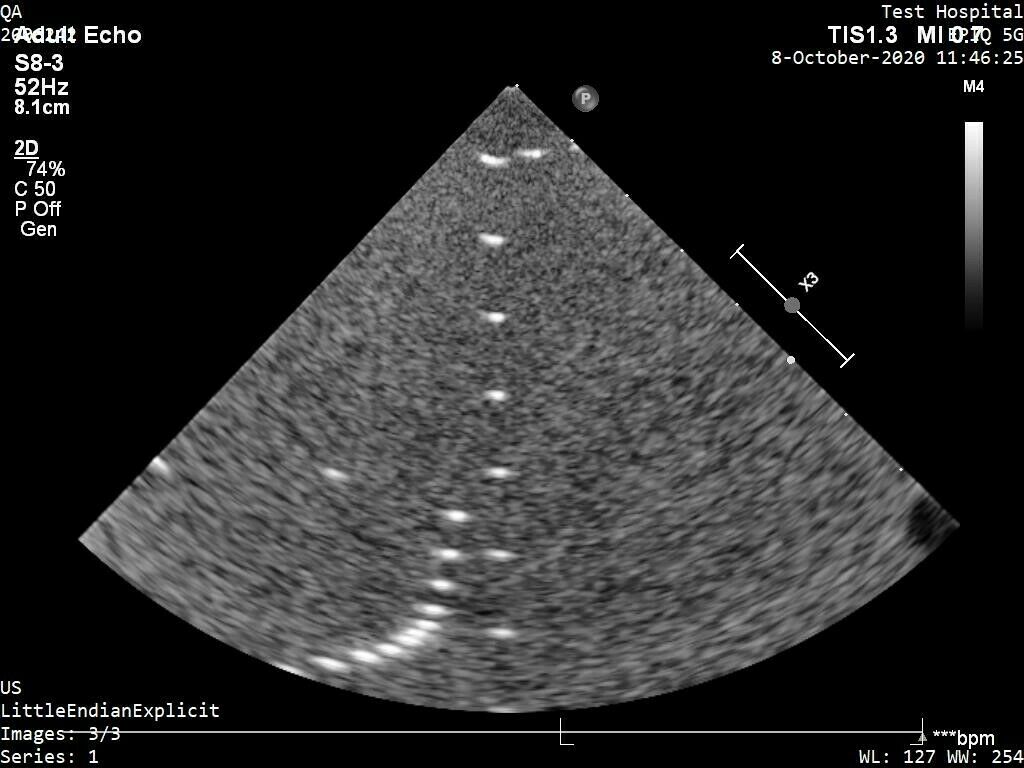

PHILIPS S12-4 ULTRASOUND TRANSDUCER PROBE

Sale price$ 4,305.00